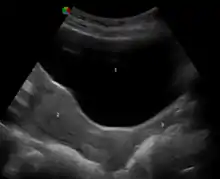

During sexual arousal, and particularly the stimulation of the clitoris, the walls of the vagina lubricate. This begins after ten to thirty seconds of sexual arousal, and increases in amount the longer the woman is aroused.[80] It reduces friction or injury that can be caused by insertion of the penis into the vagina or other penetration of the vagina during sexual activity. The vagina lengthens during the arousal, and can continue to lengthen in response to pressure; as the woman becomes fully aroused, the vagina expands in length and width, while the cervix retracts.[80][81] With the upper two-thirds of the vagina expanding and lengthening, the uterus rises into the greater pelvis, and the cervix is elevated above the vaginal floor, resulting in tenting of the mid-vaginal plane.[80] This is known as the tenting or ballooning effect.[82] As the elastic walls of the vagina stretch or contract, with support from the pelvic muscles, to wrap around the inserted penis (or other object),[62] this creates friction for the penis and helps to cause a man to experience orgasm and ejaculation, which in turn enables fertilization.[83]